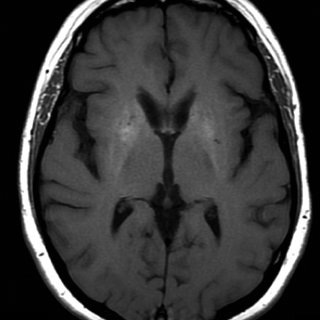

ИИ читает МРТ мозга за секунды и мгновенно выявляет угрозу жизни

Новая система искусственного интеллекта способна проанализировать МРТ головного мозга за считанные секунды и сразу отметить состояния, требующие неотложной помощи — от инсульта до внутричерепного кровоизлияния.

Разработку назвали Prima. В течение года команда оценила её работу на более чем 30 000 МРТ-исследований мозга.

Система показала более высокую диагностическую точность, чем другие современные ИИ-модели, по более чем 50 различным неврологическим диагнозам. Важнейшая особенность — Prima не только распознаёт патологию, но и определяет приоритетность случая.

При выявлении состояний, требующих срочного вмешательства (инсульт, кровоизлияние, массивный отёк), система автоматически оповещает профильного специалиста — сосудистого невролога или нейрохирурга — сразу после завершения сканирования.